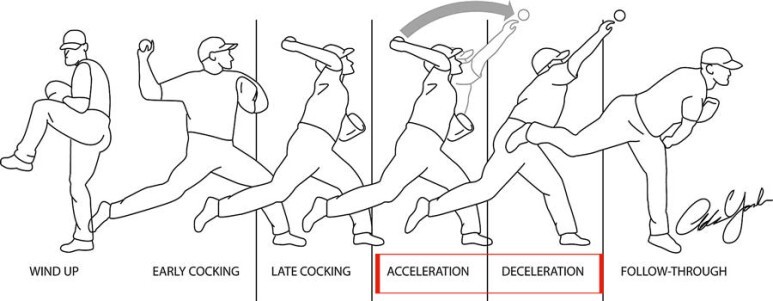

반면 어깨 뒤쪽은 상대적으로 관절와와 상완골두가 좁아지며 외회전, 수평외전 시 극상근, 극하근이 관절와순과 충돌이 많아지며 내적충돌을 일으킬 수 있습니다.(Internal impingement) 이 때 내적충돌은 전상방, 후상방에서 각각 일어날 수 있고, 주로 후상방에서 나타납니다.

참고로 내적충돌증후군은 어깨후방의 관절낭의 구축에 의해서 발생되며, 야구에서 투수가 공을 반복적으로 던지면서 생길 수 있습니다.

공을 던지거나, 라켓운동을 하는 경우에는 던지는 동작을 우선 제한하고, 견갑골 주위 근육의 강화와 운동범위 회복 후 운동하도록 합니다.